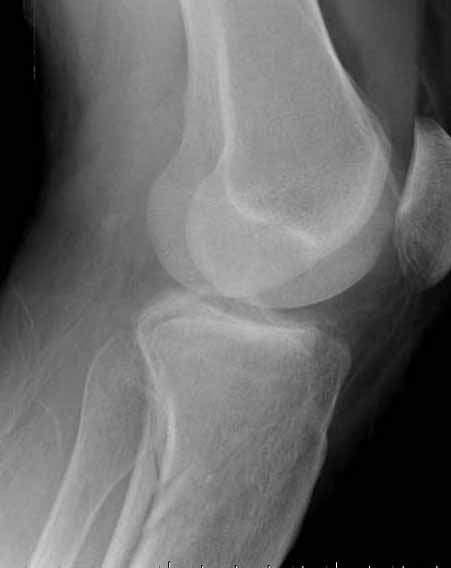

В приложении этапы фиксации пластиной Synthes для плеча при переломе медиального мыщелка.

Имя     : 1 medial column tibial plateau.JPG

Имя     : 2 medial column tibial plateau.JPG

Имя     : 4 medial column tibial plateau.JPG

Имя     : 7 medial column tibial plateau.JPG

Имя     : 8 medial column tibial plateau.JPG